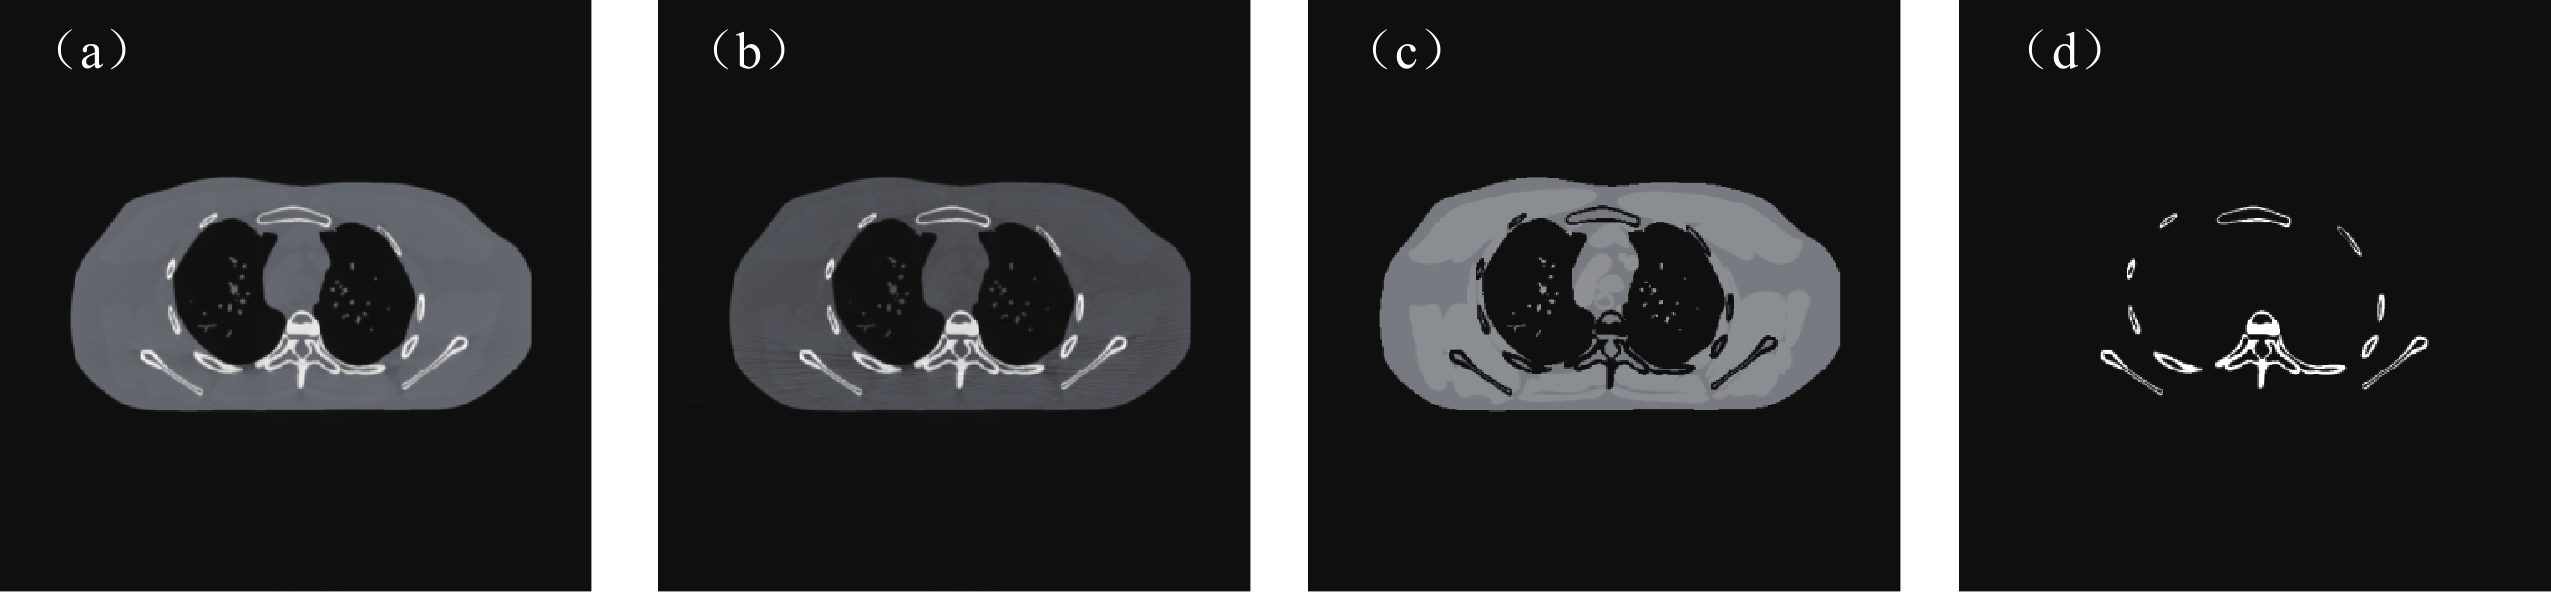

为了直观的说明IR-Net网络的去噪性能,本文选取不同于训练数据的切片77来作测试,图2显示了该切片重建的高低能图像和材料密度图像。在仿真实验中将与DIMD、DECT-ST、DECT-MULTRA进行比较,同时使用均方根误差(RMSE)、峰值信噪比(PSNR)和结构相似度(SSIM)等指标定量的分析不同算法的分解效果。